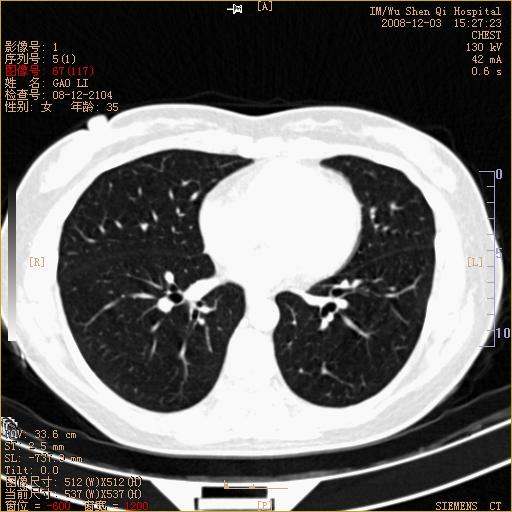

标题: CT16895:女,35岁,反复咳嗽数月,只传部分图像,是否考虑 [打印本页]

标题: CT16895:女,35岁,反复咳嗽数月,只传部分图像,是否考虑

左下肺支扩

典型“印戒征”。

印戒征,支持支扩.

左下肺扩支

印戒征,支扩